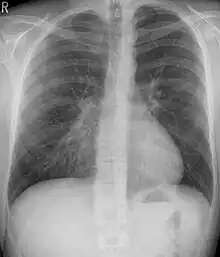

Pectus excavatum is a structural deformity of the anterior thoracic wall in which the sternum and rib cage are shaped abnormally. This produces a caved-in or sunken appearance of the chest. It can either be present at birth or develop after puberty.

The hallmark of the condition is a sunken appearance of the sternum. The most common form is a cup-shaped concavity, involving the lower end of the sternum; a broader concavity involving the upper costal cartilages is possible.[2] The lower-most ribs may protrude ("flared ribs").[3] Pectus excavatum defects may be symmetric or asymmetric.

In mild cases, cardiorespiratory function is normal, although the heart can be displaced and/or rotated.[5] In severe cases, the right atrium may be compressed, mitral valve prolapse may be present, and physical capability may be limited due to base lung capacity being decreased.[6][7]